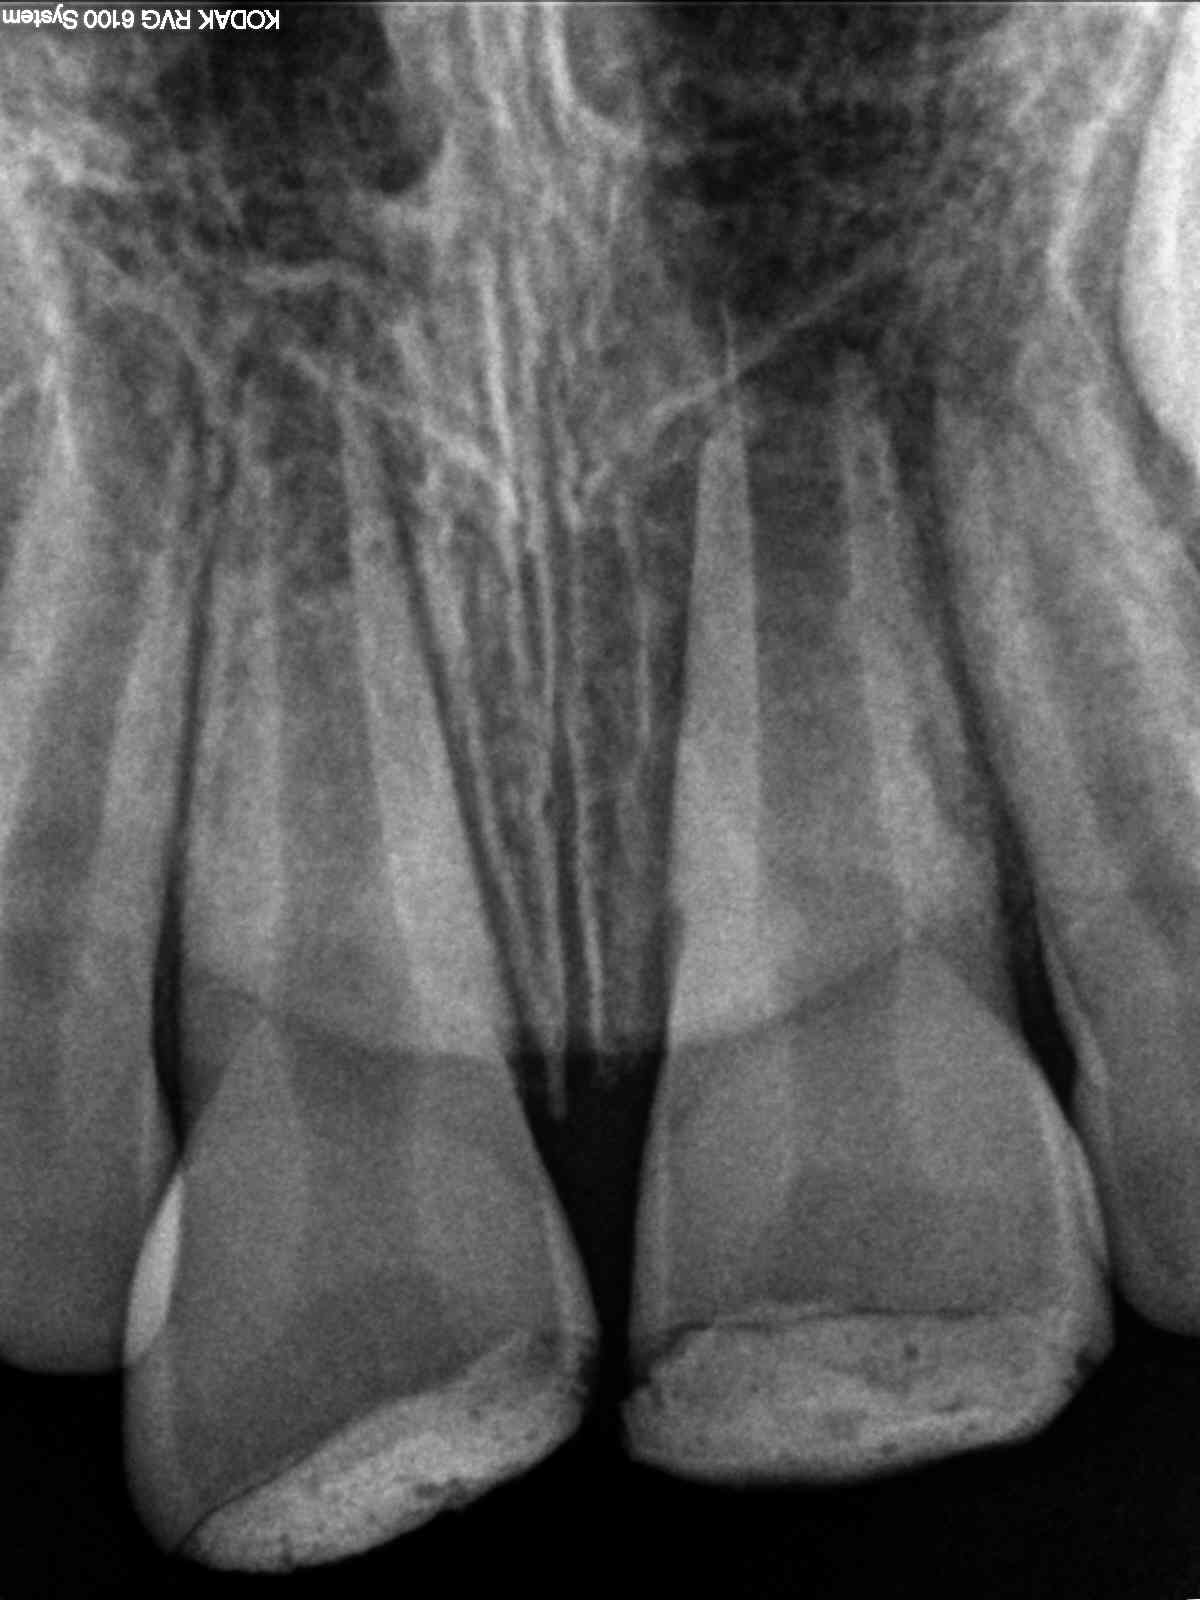

Revitalisierung – Recall nach 5,5 Jahren